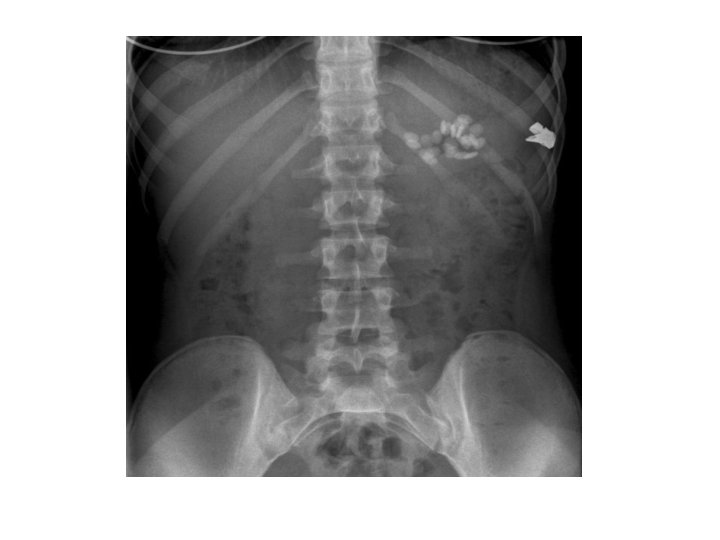

Kidney Stones • Mostly radiopaque • Calcium, cystine , uric acid and struvite stones • Aetiology : hyperparathyroidism hyperoxaluria, high citrate level, vitamin A deficiency, pyelonephritis, prolonged immobilisation,

Kidney Stones • • Increased fluid intake Medical : Nifedipine, tamsulosin Minimal Invasive surgery : ESWL, PNL Open Surgeries: Open Nephrolithotomy